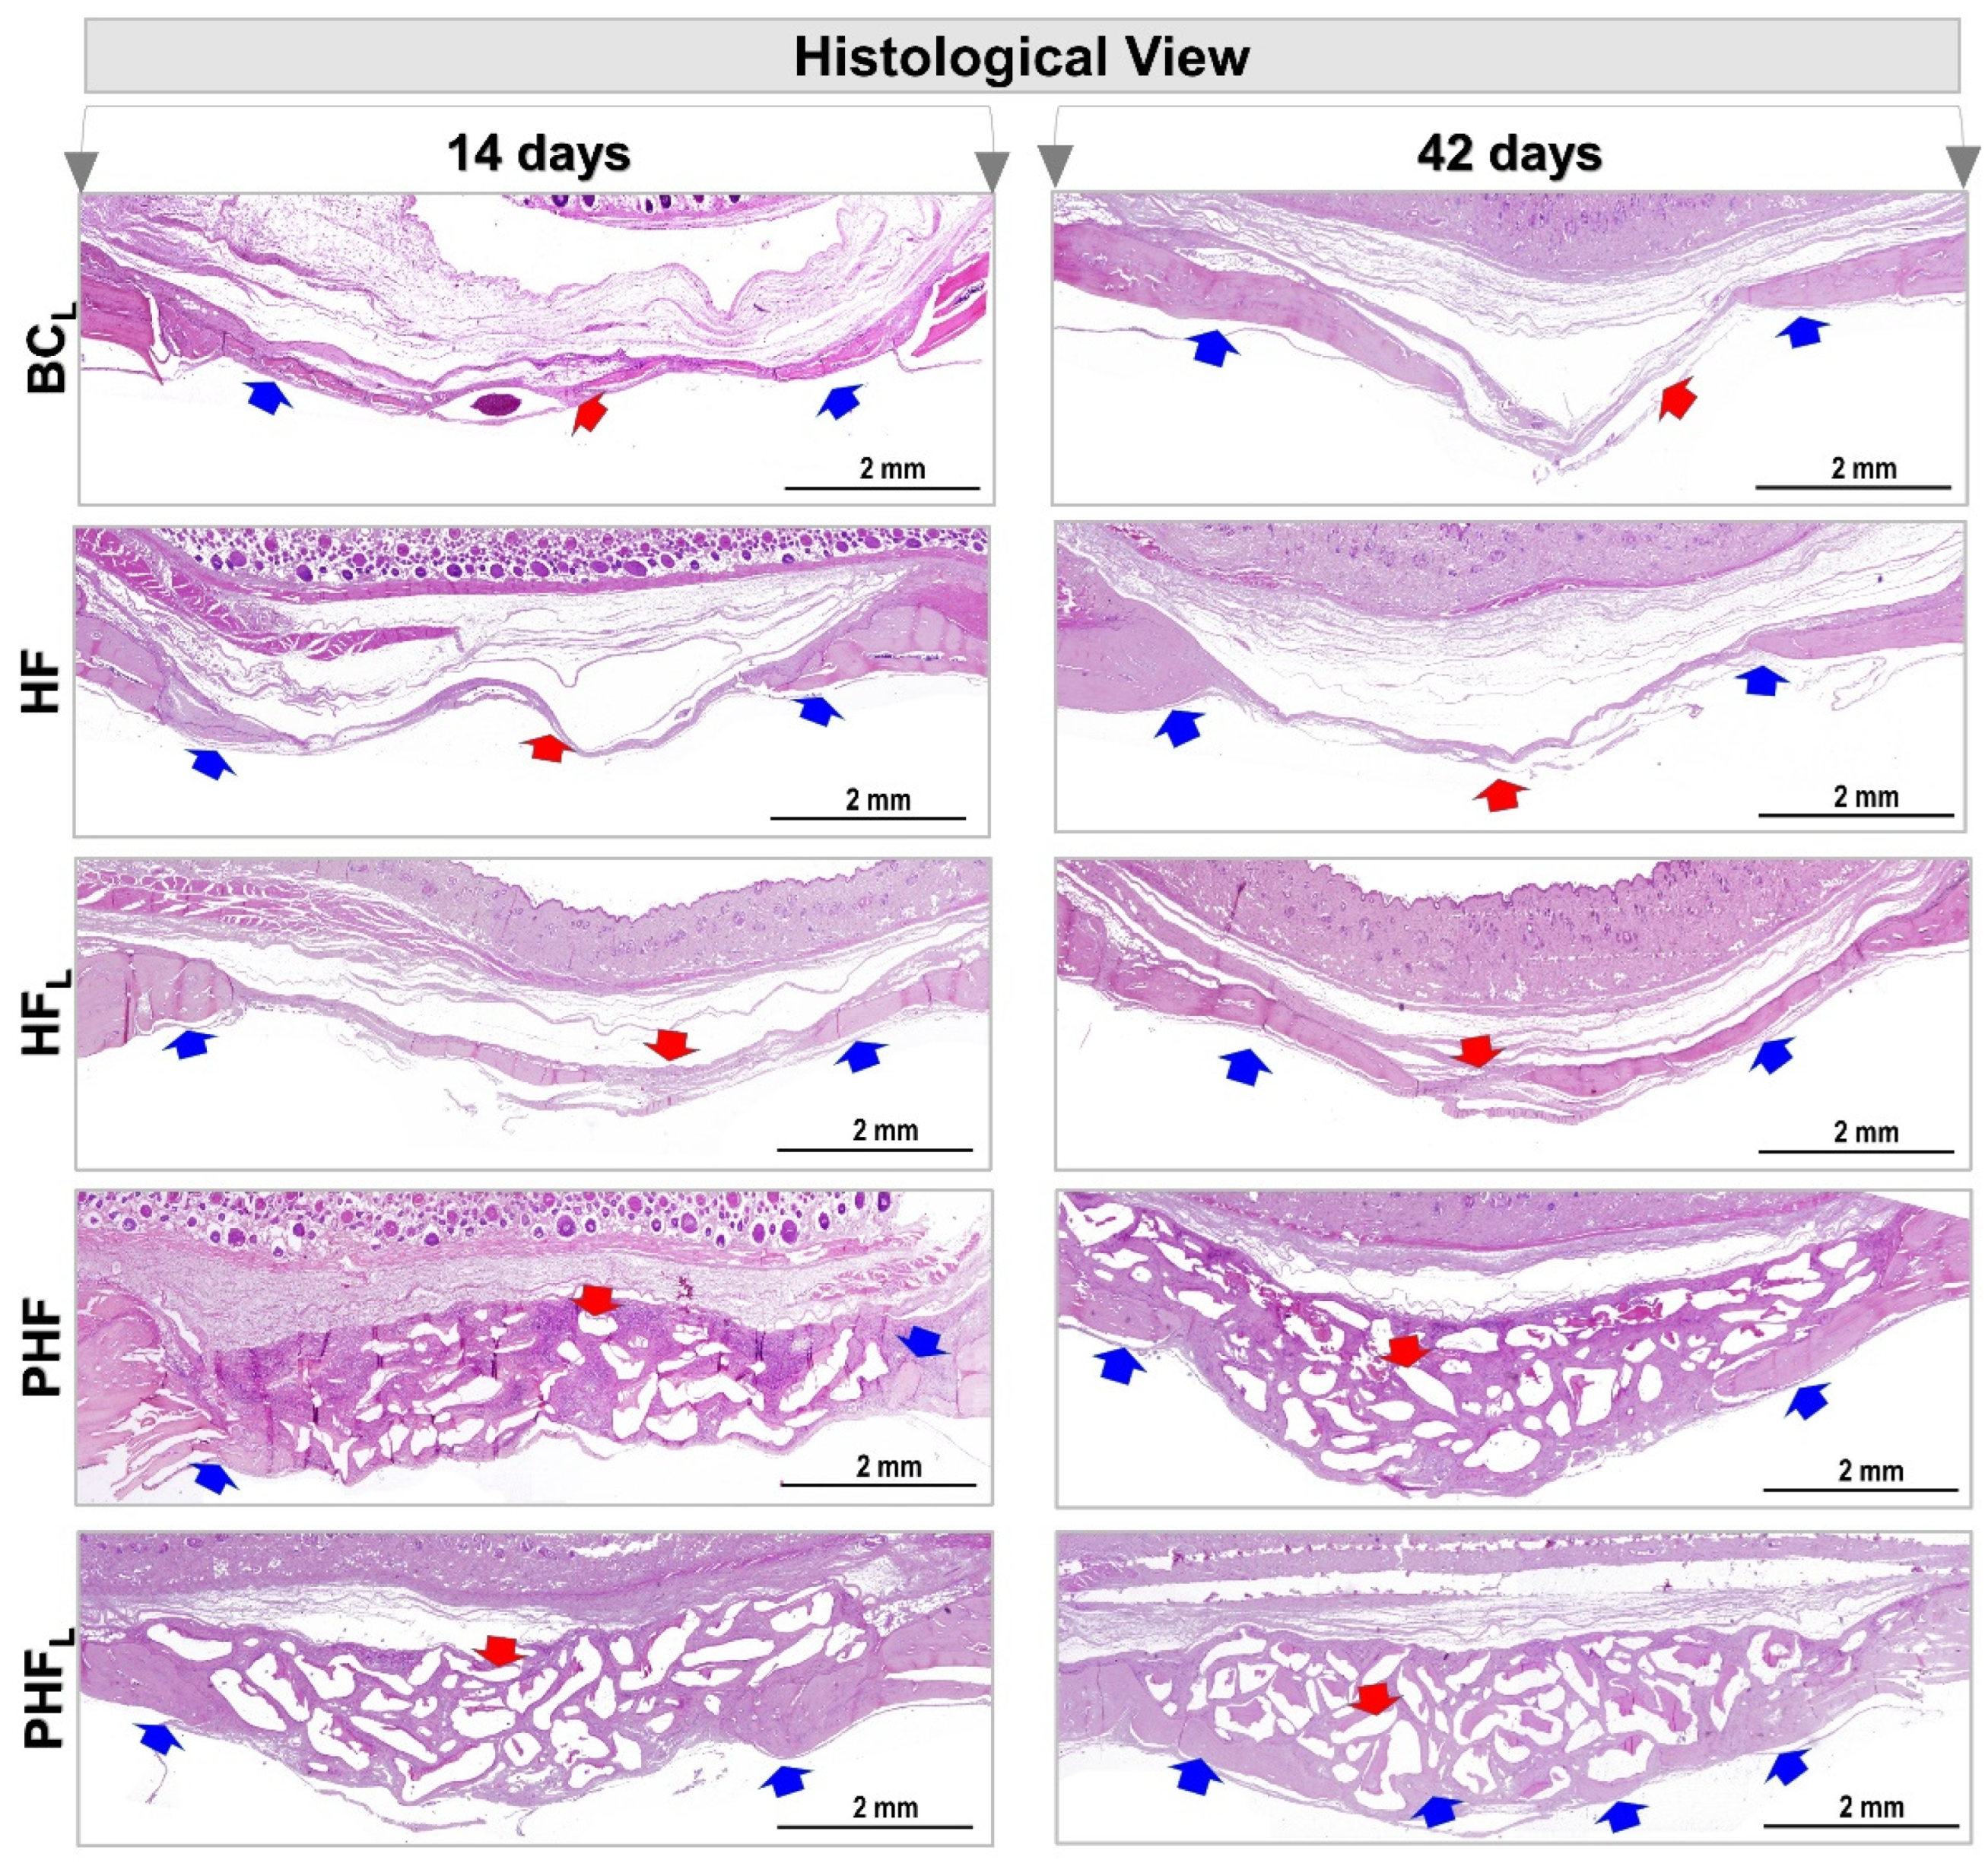

2.2. Histomorphological Analysis

4.8. Histotechnical Processing

4.9. Histomorphometric Analysis of HE-Stained Defects